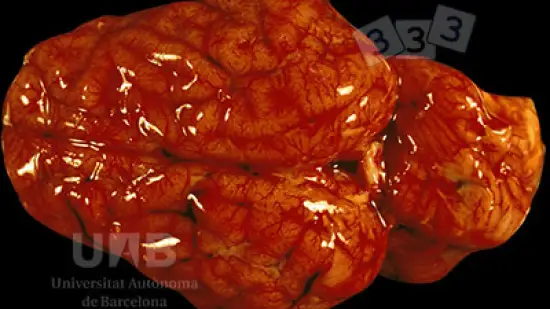

Qual é a causa desta lesão num porco com 12 semanas de idade e que acabou de morrer?